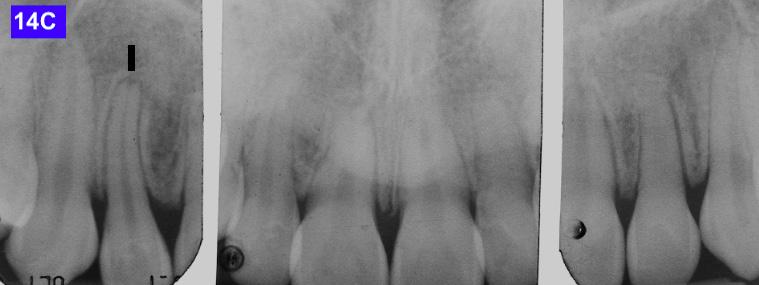

4-A, Figure 3A: The patient transferred to our office, frontal view Figure 3B: The patient transferred to our office, maxilla, occlusal view Figure 3C: The patient transferred to our office, mandible, occlusal view Figure 4A: OCS, frontal view Figure 4B: Hyrax, occlusal view Figure 4C: Retraction of maxillary lateral incisors

Figure 14C: Post-treatment periapical radiograms

Please view the post-treatment images at the time of insertion of the retainers (Figure 14 - A, B, C. D, E, F, G, H, I, J, K, L, M, N).9